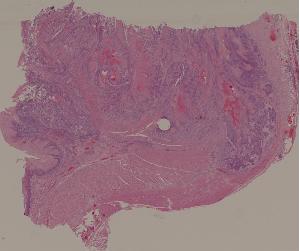

27.食管鳞形细胞癌